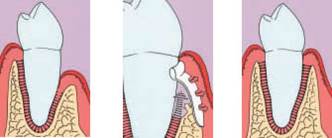

Jedná se o vyzvednutí membrány, která čelistní dutinu vystýlá, pod vyzvednutou membránou vznikne kapsa, kam se umístí augmentační materiál, do kterého se zavedou implantáty.

- Uzavřený, interní, vnitřní, crestální sinus lift

- Otevřený, externí, vnější, laterální sinus lift